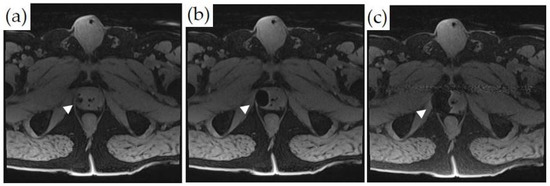

3.3. MRI-Guided Cryoablation